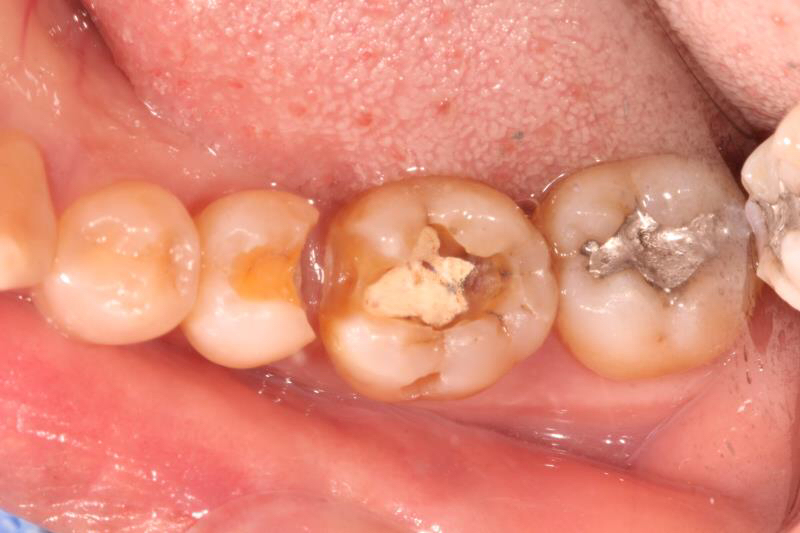

患者多年前银汞充填,因边缘微渗漏导致继发龋坏,我院采用相较于传统补牙更耐用、美观、可承受更大咬合力的修复方式:嵌体修复。